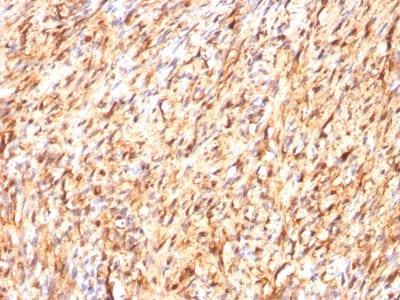

S100 belongs to the family of calcium binding proteins. S100A and S100B proteins are two members of the S100 family. S100A is composed of an alpha and a beta chain whereas S100B is composed of two beta chains. This antibody is specific against an epitope located on the beta-chain (i.e. in S-100A and S-100B) but not on the alpha-chain of S-100 (i.e. in S-100A and S100A0). This antibody can be used to localize S-100A and S-100B in various tissue sections. S-100 protein has been found in normal melanocytes, Langerhans cells, histiocytes, chondrocytes, lipocytes, skeletal and cardiac muscle, Schwann cells, epithelial and myoepithelial cells of the breast, salivary and sweat glands, as well as in glial cells. Neoplasms derived from these cells also express S-100 protein, albeit non-uniformly. A large number of well-differentiated tumors of the salivary gland, adipose and cartilaginous tissue, and Schwann cell-derived tumors express S-100 protein. Almost all malignant melanomas and cases of histiocytosis X are positive for S-100 protein.Primary antibodies are available purified, or with a selection of fluorescent CF® Dyes and other labels. CF® Dyes offer exceptional brightness and photostability. Note: Conjugates of blue fluorescent dyes like CF®405S and CF®405M are not recommended for detecting low abundance targets, because blue dyes have lower fluorescence and can give higher non-specific background than other dye colors.

Positive Control

Brain, Melanoma

Melanoma

IF (verified), IHC, FFPE (verified)

IF (verified)|IHC (FFPE) (verified)

Higher concentration may be required for direct detection using primary antibody conjugates than for indirect detection with secondary antibody|Immunofluorescence: 1-2 ug/mL|Immunohistology formalin-fixed 0.25-0.5 ug/mL|Staining of formalin-fixed tissues requires boiling tissue sections in 10 mM citrate buffer, pH 6.0, for 10-20 min followed by cooling at RT for 20 minutes|Flow Cytometry 0.5-1 ug/million cells/0.1 mL|Western blotting 0.5-1 ug/mL|Optimal dilution for a specific application should be determined by user